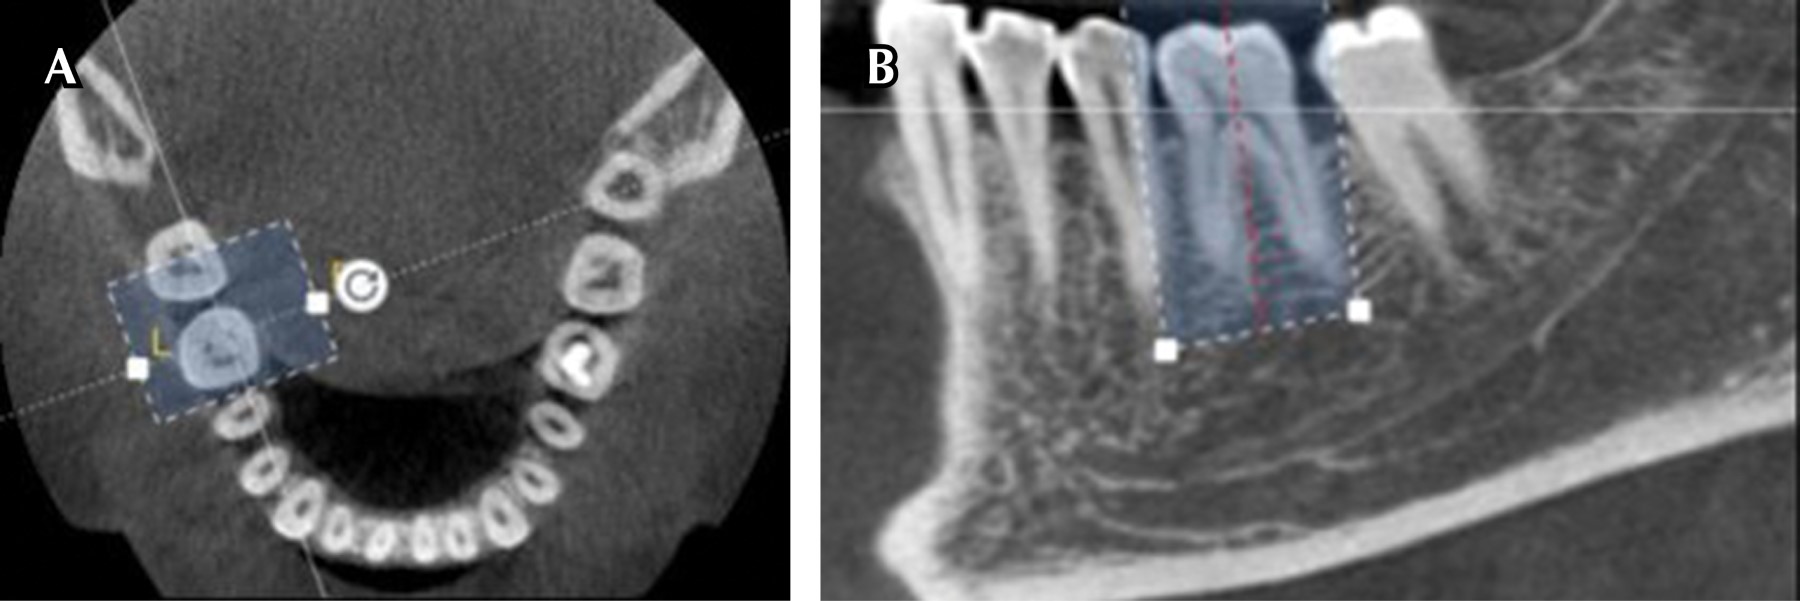

Para poder observar cada muestra, se requirió separar digitalmente las imágenes tomográficas de cada una de ellas del resto de los componentes anatómicos de cada paciente visibles en la tomografía, para ello, por medio del programa 3D EndoTM (Dentsply/Sirona USA), se recortó la imagen de cada molar en los planos axial, coronal y sagital (Figura 1).

Una vez individualizado cada molar, se procedió a trazar la trayectoria corono-apical, tanto del conducto mesio-bucal (MB), como del mesio-lingual (ML), para ello se empleó la herramienta de selección de conductos del software, por medio de esta herramienta se ubican marcas con forma de gota invertida, tanto en la zona coronal como apical de ambos conductos, el programa ofrece colores diferentes de estas figuras para identificarlas, la posición de estas marcas se controla visualmente en forma simultánea, en los planos coronal, sagital y axial, la colocación de cada marca puede ajustarse de forma manual (Figura 2).

Una vez hecho lo anterior, el software identifica la trayectoria de cada conducto y el operador puede elegir cuál de los dos conductos desea observar, al seleccionar un conducto, el programa presenta una pantalla con imágenes de éste en sentido axial, sagital y coronal, además de una reconstrucción de todo el molar en 3D (Figura 3).